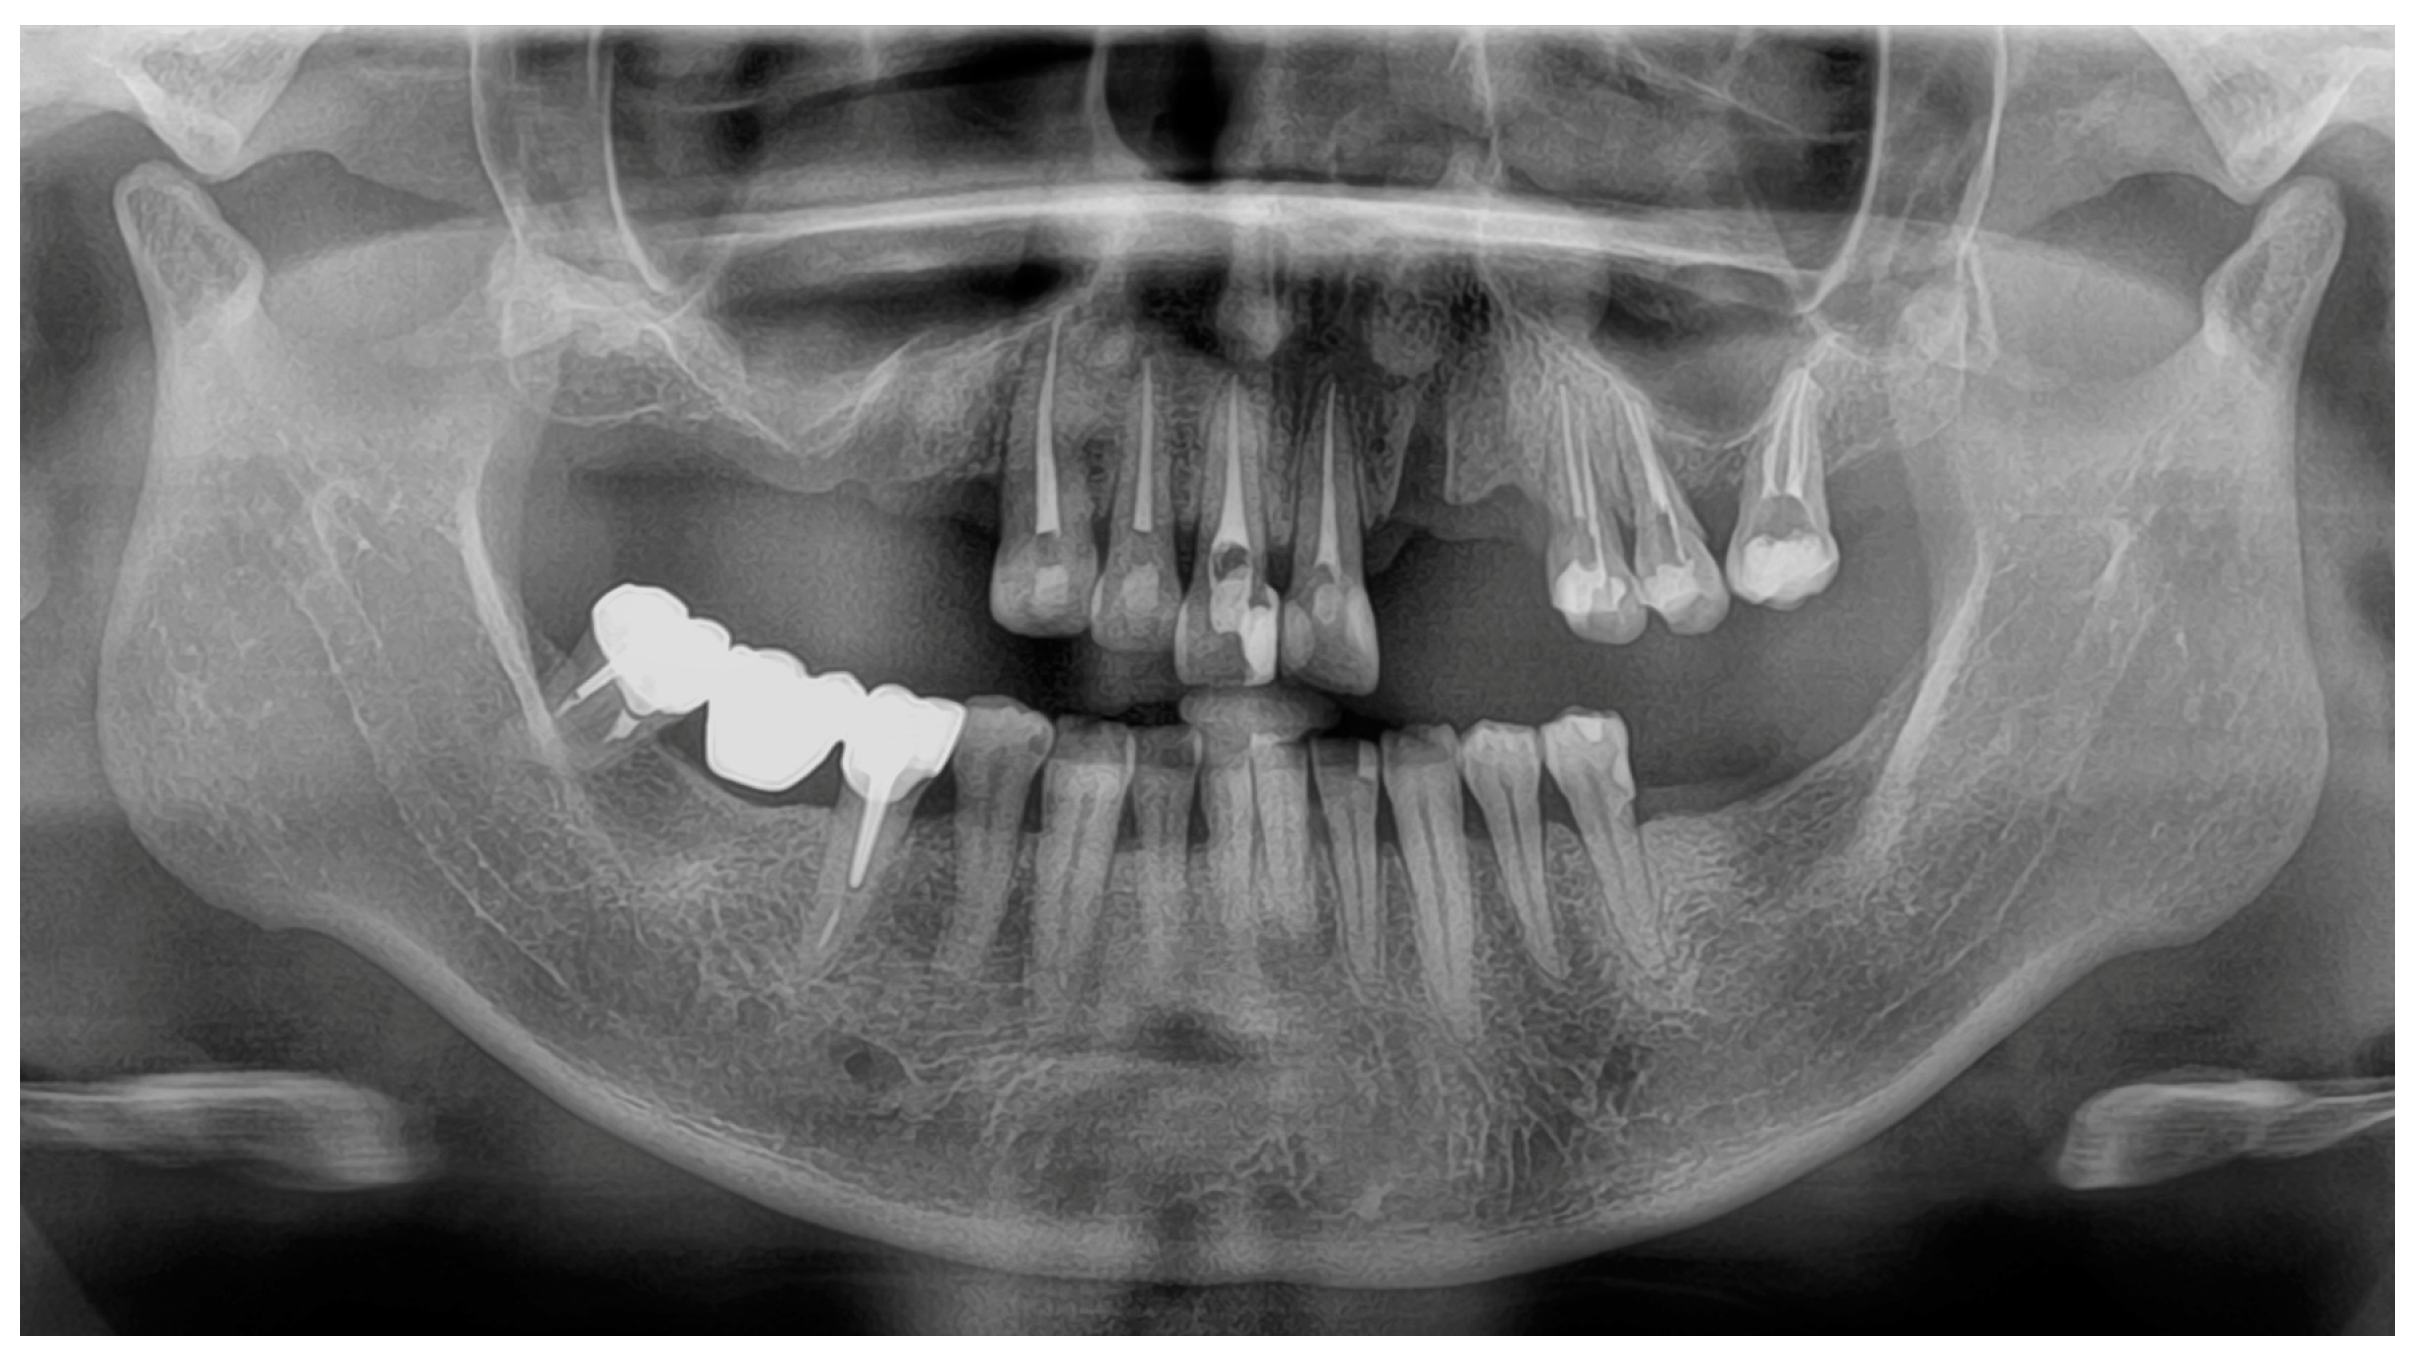

Clinical investigations showed partially edentulous regions of the maxilla (Kennedy class II, #14-17, #22-23, #27) and mandible (Kennedy class II, #36-37). Tooth #13 had a significant vestibular cervical lesion and the maxillary teeth had several composite restorations. Tooth #12 had a mesio-palatal rotation and tooth #44 had a slight extrusion. In the mandible, a satisfactory metal bridge replaced tooth #46. No alteration of the vertical dimension of occlusion (OVD) was observed. The smile line only revealed gingival embrasures (Class III according to Liébart classification). The patient did not wish to correct the misaligned gingival margins of the maxillary central incisors. The panoramic radiograph revealed that all the maxillary residual teeth had been treated endodontically, and teeth #15 and #22 had recently been removed (Figure 1). Tooth #27 was mesially positioned in place of tooth #26 probably due to an uncompensated extraction in the past.

Figure 1.

Initial panoramic radiography.